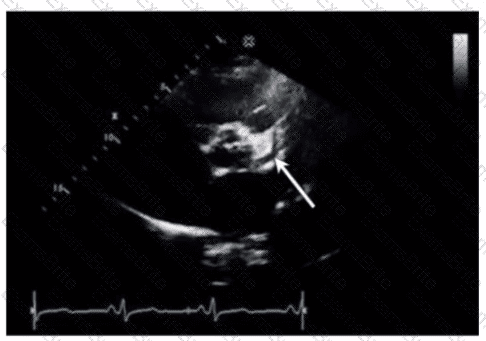

Which is the most likely abnormality represented in these images from a 48-year-old man with shortness of breath?